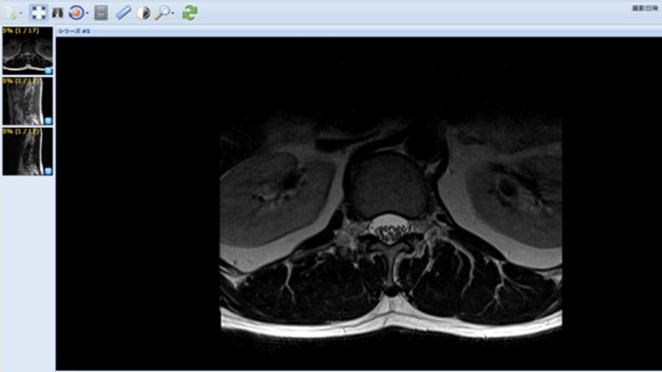

検査画像も即座に確認

ID-LinkのViewerを用いて検査画像を確認できます。このViewerでは簡易的な機能を搭載していますが、DICOMファイルをダウンロードすることができるため自院のPACSに取り込んで、 より詳細に確認するといった活用も可能です。これにより患者にCD-Rを持たせる必要はなくなり、紹介された医療機関側でもCD-Rの保管スペースの確保や管理が不要となります。